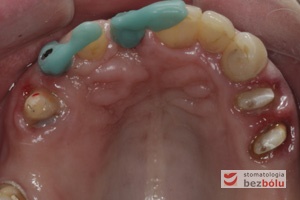

Powierzchnie okluzyjne górnego łuku zębowego - zęby szczęki przygotowane zachowawczo do dobudowy implanto-protetycznej

Powierzchnie okluzyjne górnego łuku zębowego – zęby szczęki przygotowane zachowawczo do dobudowy implanto-protetycznej

Szablon implantologiczny na zębach szczęki - wyznaczenie właściwej pozycji dla implantów poprzez termoplastyczny nawigator

Szablon implantologiczny na zębach szczęki – wyznaczenie właściwej pozycji dla implantów poprzez termoplastyczny nawigator